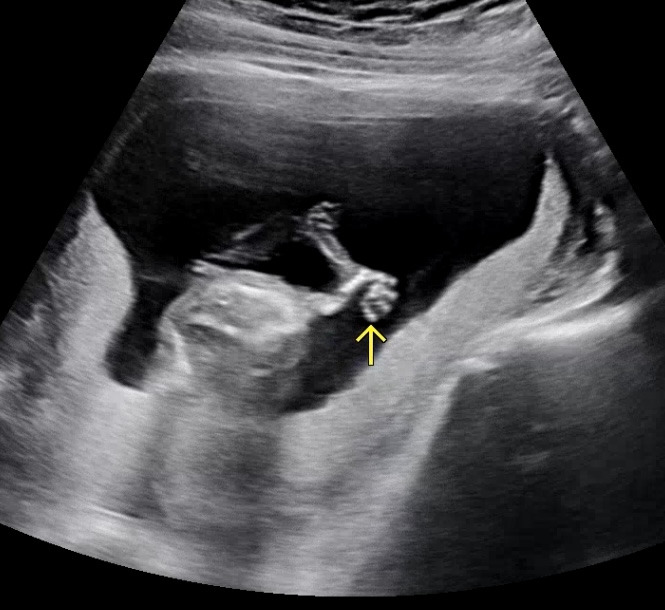

(의사선생님이 "손에 자신 있나 봐요~"라고 하실 정도로 항상 손을 많이 보여주는 우리 애기,,ㅎㅎ)